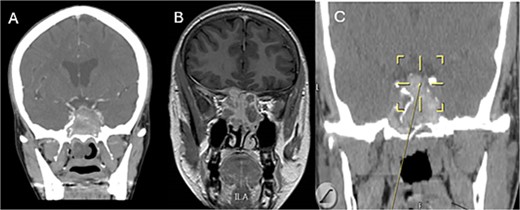

A 69-years-old diabetic female was referred from neurology as she complained of an acute onset severe headache, diplopia, and retro-orbital pressure. An initial CT scan with a subsequent MRI scan (Fig. 5) showed infiltrative sphenoid pathology invading both skull base and cavernous sinus given a provisional diagnosis of acute invasive fungal sinusitis. The patient was urgently taken to the operative theater to endoscopically debride sphenoid sinuses (Fig. 6). Histopathological examination confirmed the diagnosis of invasive sphenoid sinus mucormycosis.

Coronal CT (A) and MRI (B) and CT image guided intra-operative (C) images of the paranasal sinuses showing aggressive sphenoid sinus disease extending to the skull base and cavernous sinus.

Intra-operative endoscopic view of shenoid sinus debridement of invasive fungal disease.